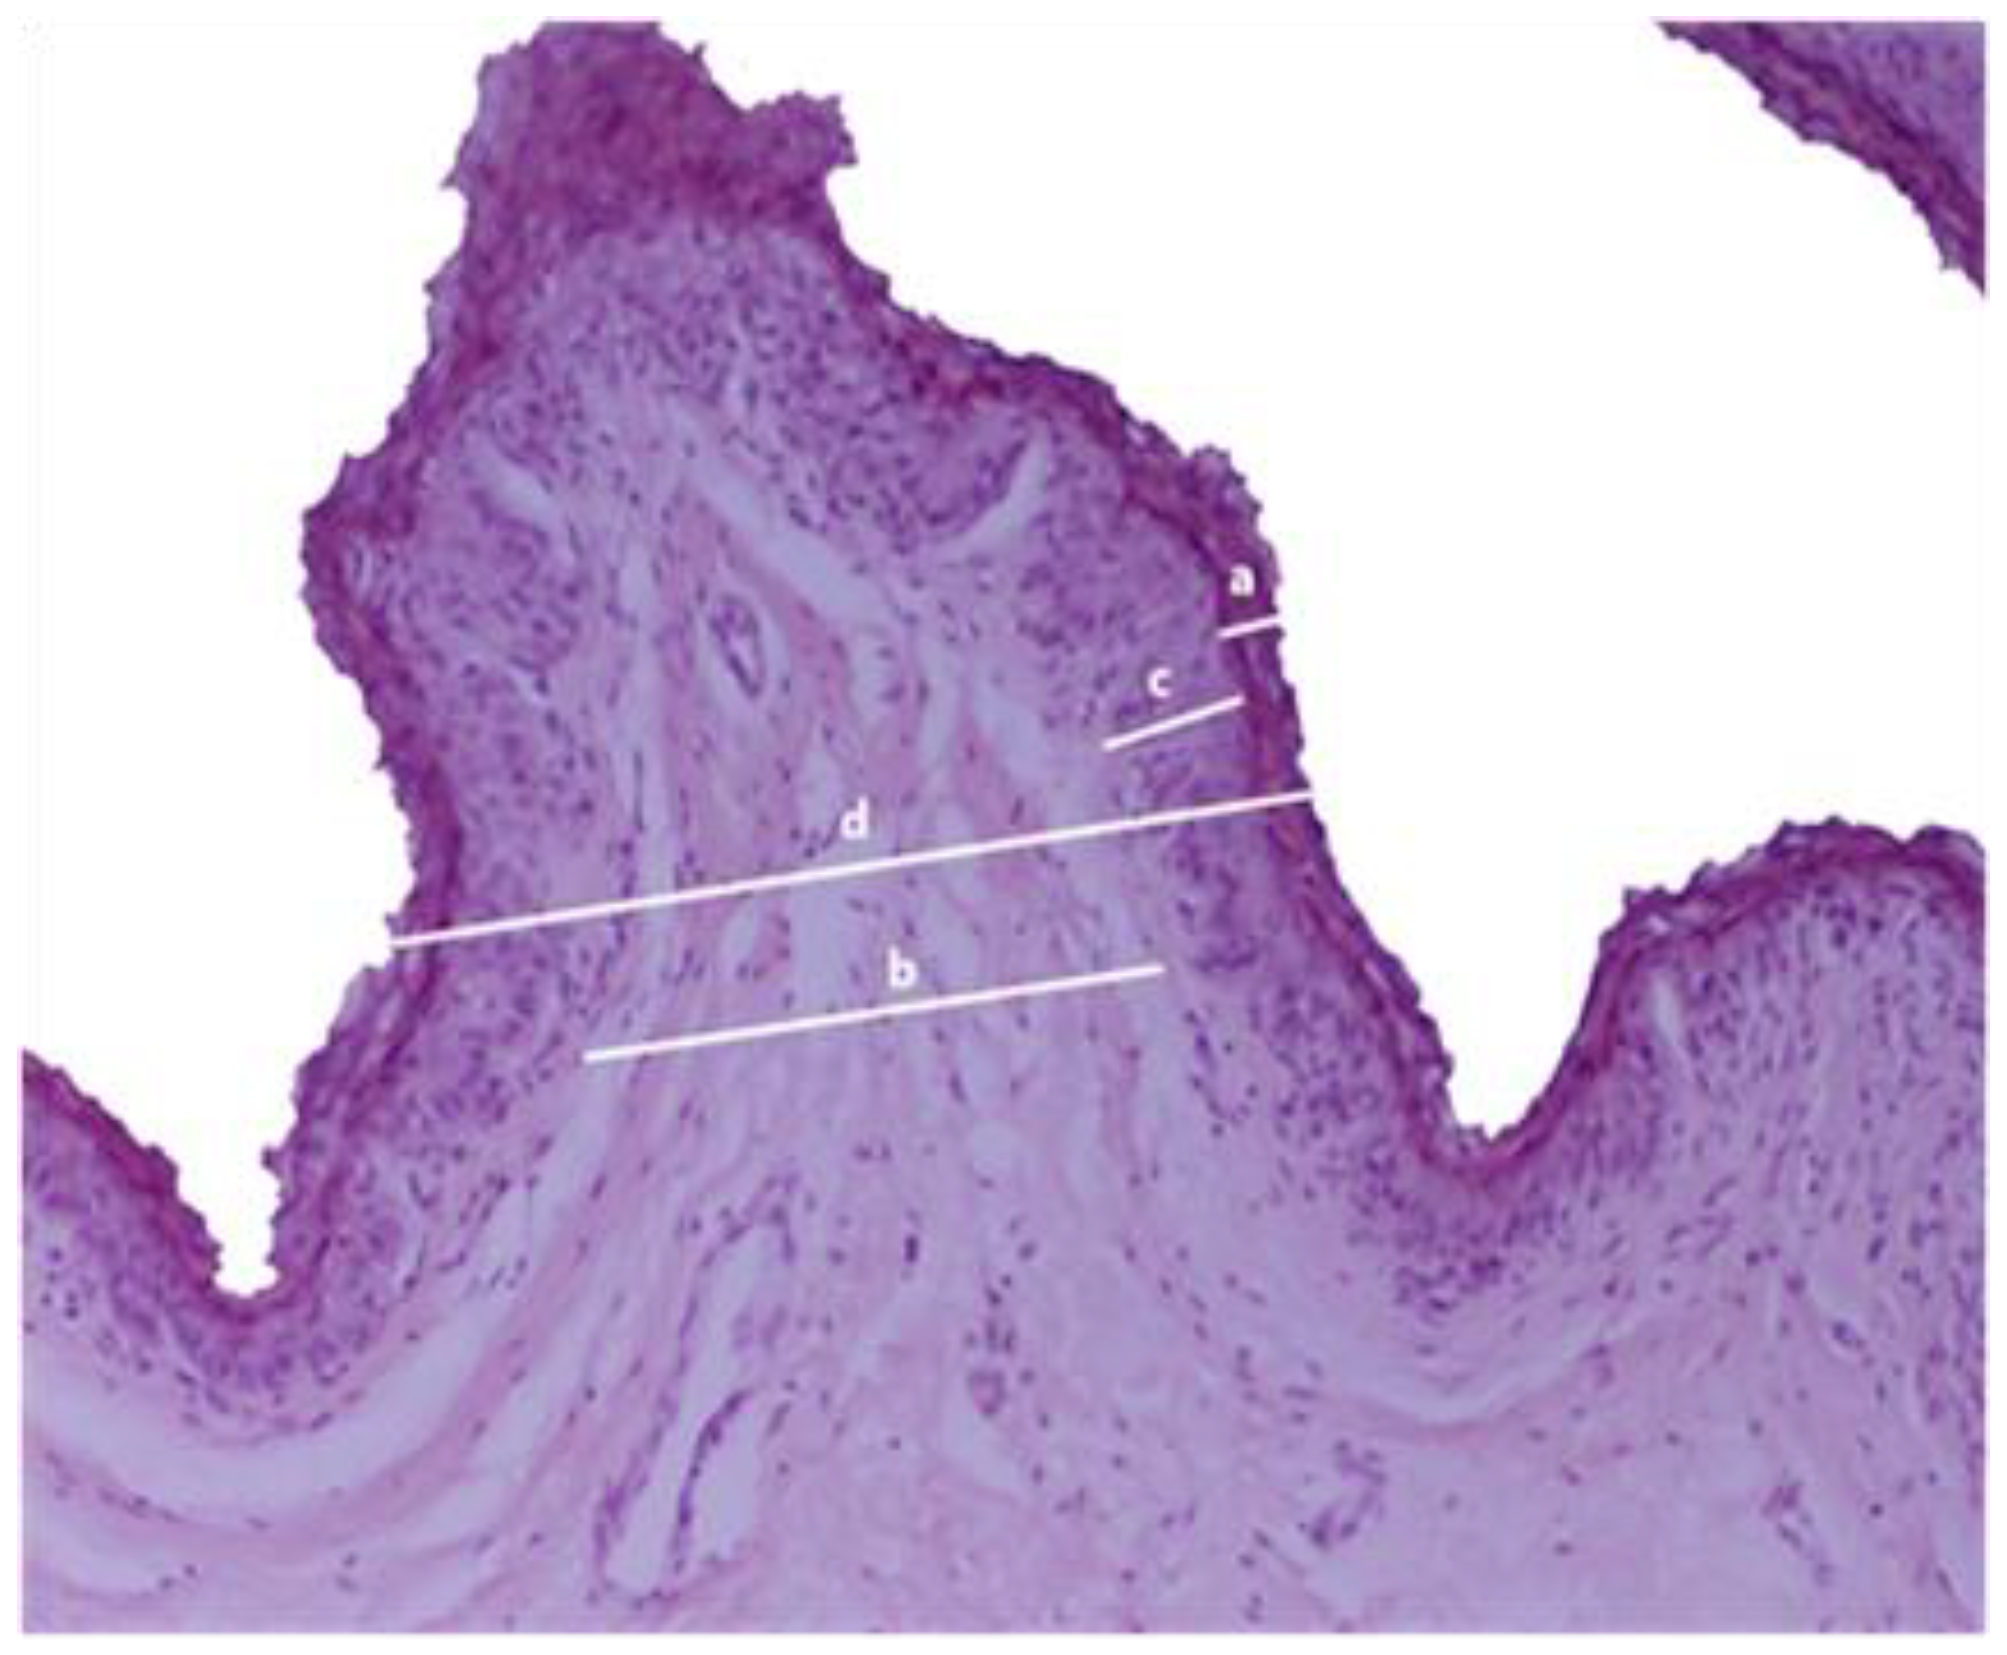

2.5.5. Histological Examination

3.3. Ruminal Epithelium Histopathology and Histomorphometry

| Ruminal Epithelium | Category 1 i (n = 15) | Category 2 ii (n = 15) | Category 3 iii (n = 15) | p-Value |

|---|---|---|---|---|

| Stratum corneum (μm) | 33.67 ± 12.83 | 43.07 ± 24.97 | 41.67 ± 16.25 | 0.342 |

| Connective tissue (μm) | 103.27 ± 39.35 | 135.00 ± 61.32 | 148.13 ± 63.83 | 0.090 |

| Non-keratinized epithelium (μm) | 80.13 ± 14.46 | 116.47 ± 28.64 | 166.67 ± 21.41 | <0.001 |

| Total epithelium (μm) | 217.07 ± 51.69 | 294.53 ± 61.26 | 356.47 ± 74.08 | <0.001 |